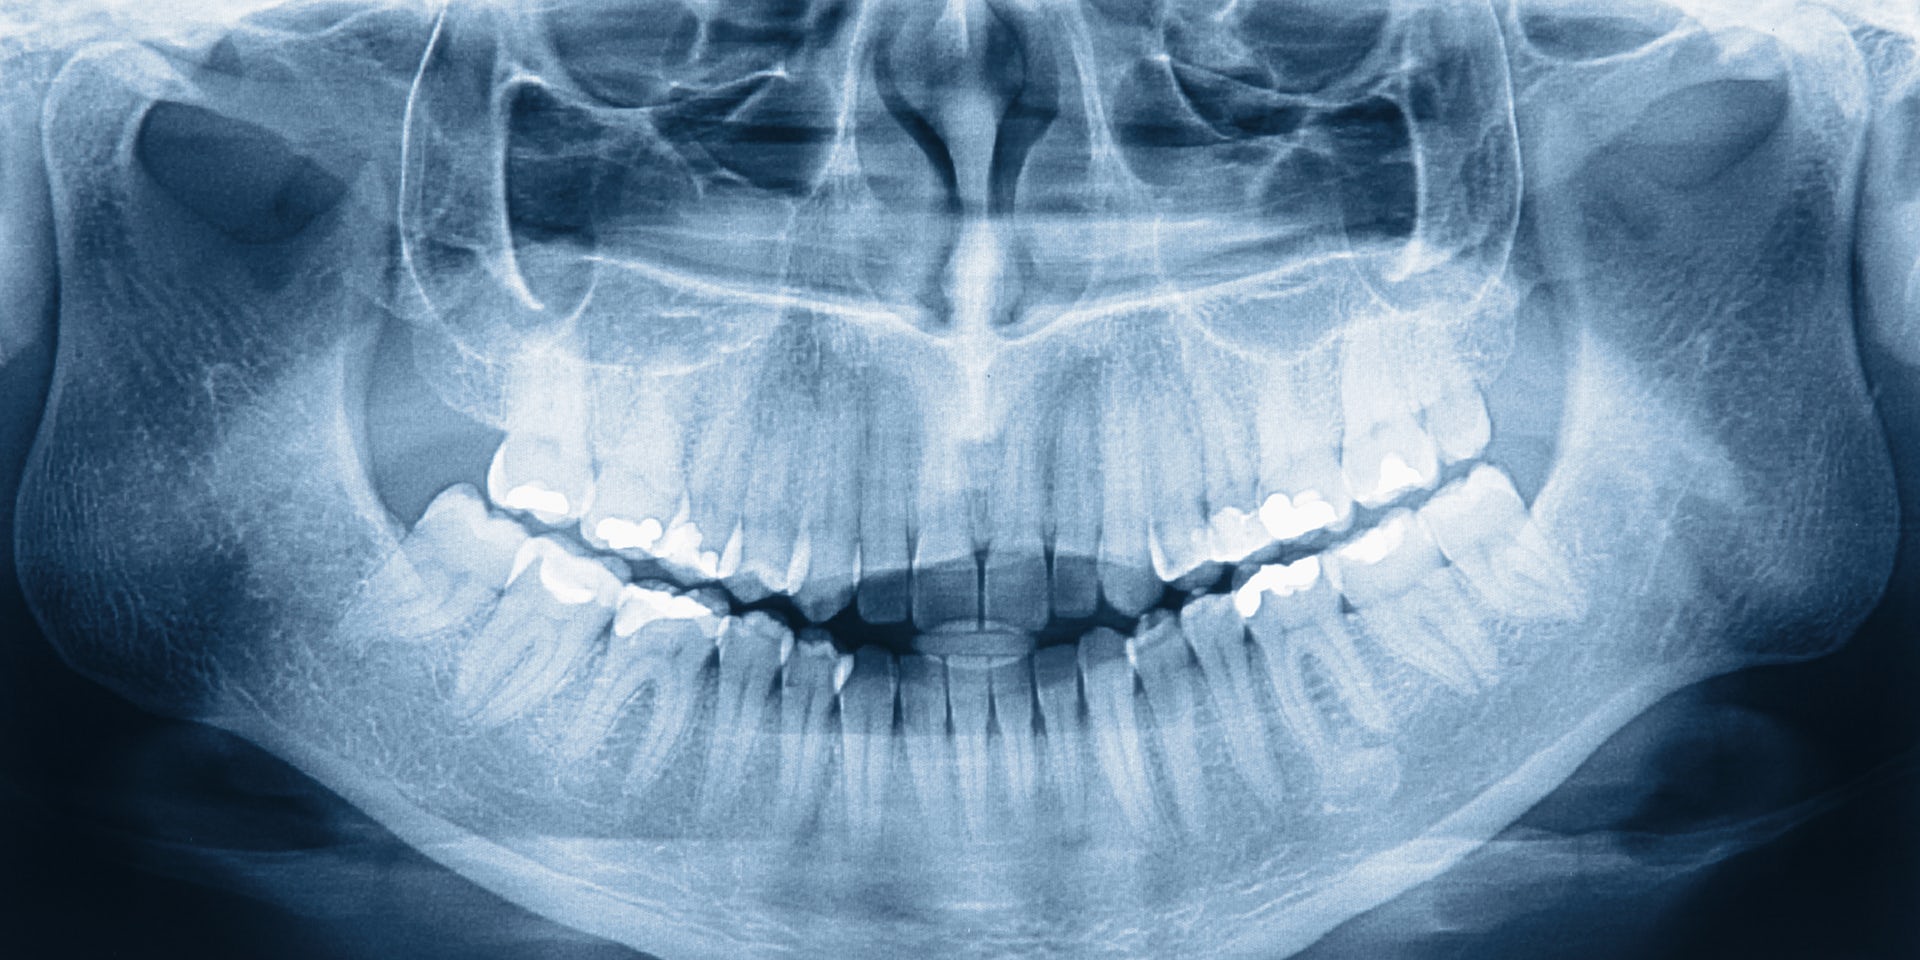

Рентгеновское изображение является основным критерием при постановке диагноза в стоматологии. Однако обычные панорамные или прицельные снимки имеют всё же ограниченный диагностический потенциал, поскольку они дают информацию лишь в двух плоскостях.

Так называется панорамный, особенный снимок всей челюстно-лицевой области, который делается за несколько минут. При ОПТГ лучевая нагрузка меньше на 90%, чем при проведении стандартного рентгена. Зато объем полученной информации о состоянии зубов значительно больше. Стоимость процедуры ненамного превышает обследование на стандартном рентгеновском аппарате. ОПТГ помогает одновременно оценить состояние костной ткани зубов и пародонта.

Как известно, успешное лечение начинается с корректной диагностики. И с 1895 года медицина получила в свое распоряжение наиболее быстрый и точный способ визуализации костных тканей организма — рентгенографию. За более чем 100 лет рентгенология значительно усовершенствовалась, став неотъемлемой частью стоматологической диагностики. Сегодня с помощью рентгеновских лучей можно не просто сделать снимок зуба, беспокоящего своего владельца, но и получить панорамное изображение обеих челюстей пациента с прилегающими к ним тканями — такой снимок в стоматологической диагностике называется ортопантомограмма.

Обширные возможности ортопантомограммы в стоматологической диагностике

С помощью панорамного снимка зубов пациента его лечащий врач получит огромный и крайне ценный массив информации о здоровье пациента, включая следующие сведения:

- скрытые кариозные полости;

- степень сформирования корней зубов и их удаленность друг от друга;

- качество имеющихся пломбировок каналов;

- состояние костных тканей и пародонта;

- этап прорезывания зубов мудрости;

- наличие сверхкомплектных зубов и ретенции;

- состояние имеющихся в полости рта штифтов и несъемных зубных протезов;

- близость гайморовых пазух и нижнечелюстного нерва к зубным рядам;

- наличие кист, гранулем и невидимых при визуальном осмотре воспалений с локализацией у верхушек корней зубов.